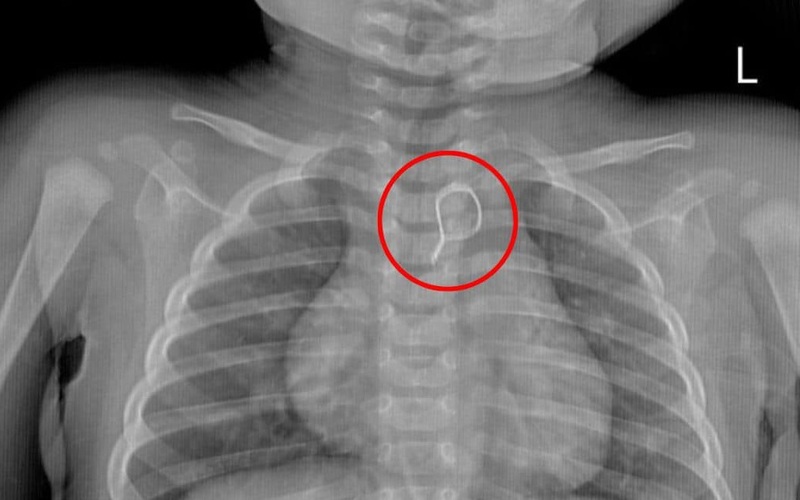

Bệnh nhi nhập viện trong tình trạng quấy khóc nhiều, tự thở đều, da niêm mạc hồng, nhịp tim rõ. Kết quả chụp X-quang cho thấy có dị vật hình tròn cản quang chồng hình trong trung thất.

Ca nội soi gắp dị vật được ThS.BS Nguyễn Quang Huy – Phó Trưởng khoa Nội tiêu hóa trực tiếp thực hiện đã diễn ra thành công. Dị vật được gắp ra là nhung bọc dây kẽm uốn tròn có 1 đầu nhọn với đường kính khoảng 1,5cm.